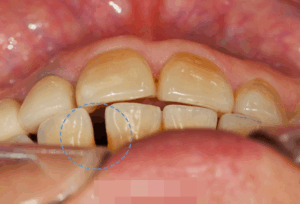

반갑습니다, 면목역 치과 글로리의 김정은 대표원장입니다. 교정이 필요한 순간들이 꽤 여럿 있습니다. 가지런하지 못한 치열을 가졌을 때도 있고, 때로는 맞지 않은 교합 관계의 문제, 그리고 뻐드러진 치열을 가질…